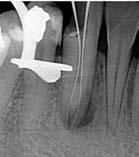

Clinical examination revealed no mobility, normal periodontium, no swelling or sinus tract, and the tooth was not tender to percussion. Pulp sensitivity testing of the tooth showed no response to cold and electrical pulp testing. Radiographic evaluation of the affected tooth revealed unusual, complex root canal anatomy. The radiographic image showed the presence of two roots with periapical radiolucency (Fig. 3).

Infiltration of the local anesthesia (Lidocaine HCl 2% with epinephrine 1:100,000) was administered and the rubber dam was placed. Access to the cavity was achieved using a round diamond bur. The conventional lingual access opening was modified by including more of the incisal surface to gain sufficient access to the canals . The two orifices were located one buccally and one lingually. Coronal flaring was carried out using the Sx file of the ProTaper system (Dentsply-Maillefer, Ballaigues, Switzerland). The two canals were carefully instrumented with a size 15 K-file . The working length of the canals was established with the use of apex locator (Root ZX: J Morita Co, Kyoto, Japan) and verified radiographically (Fig.4).

4